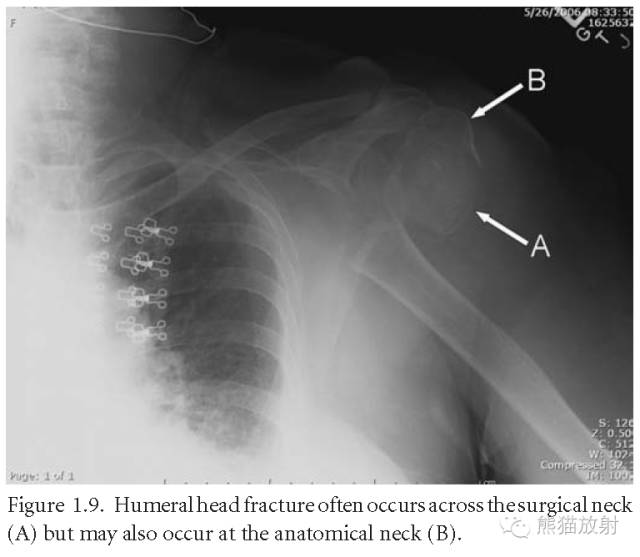

肱骨头骨折:常发生于外科颈,偶尔见于解剖颈。